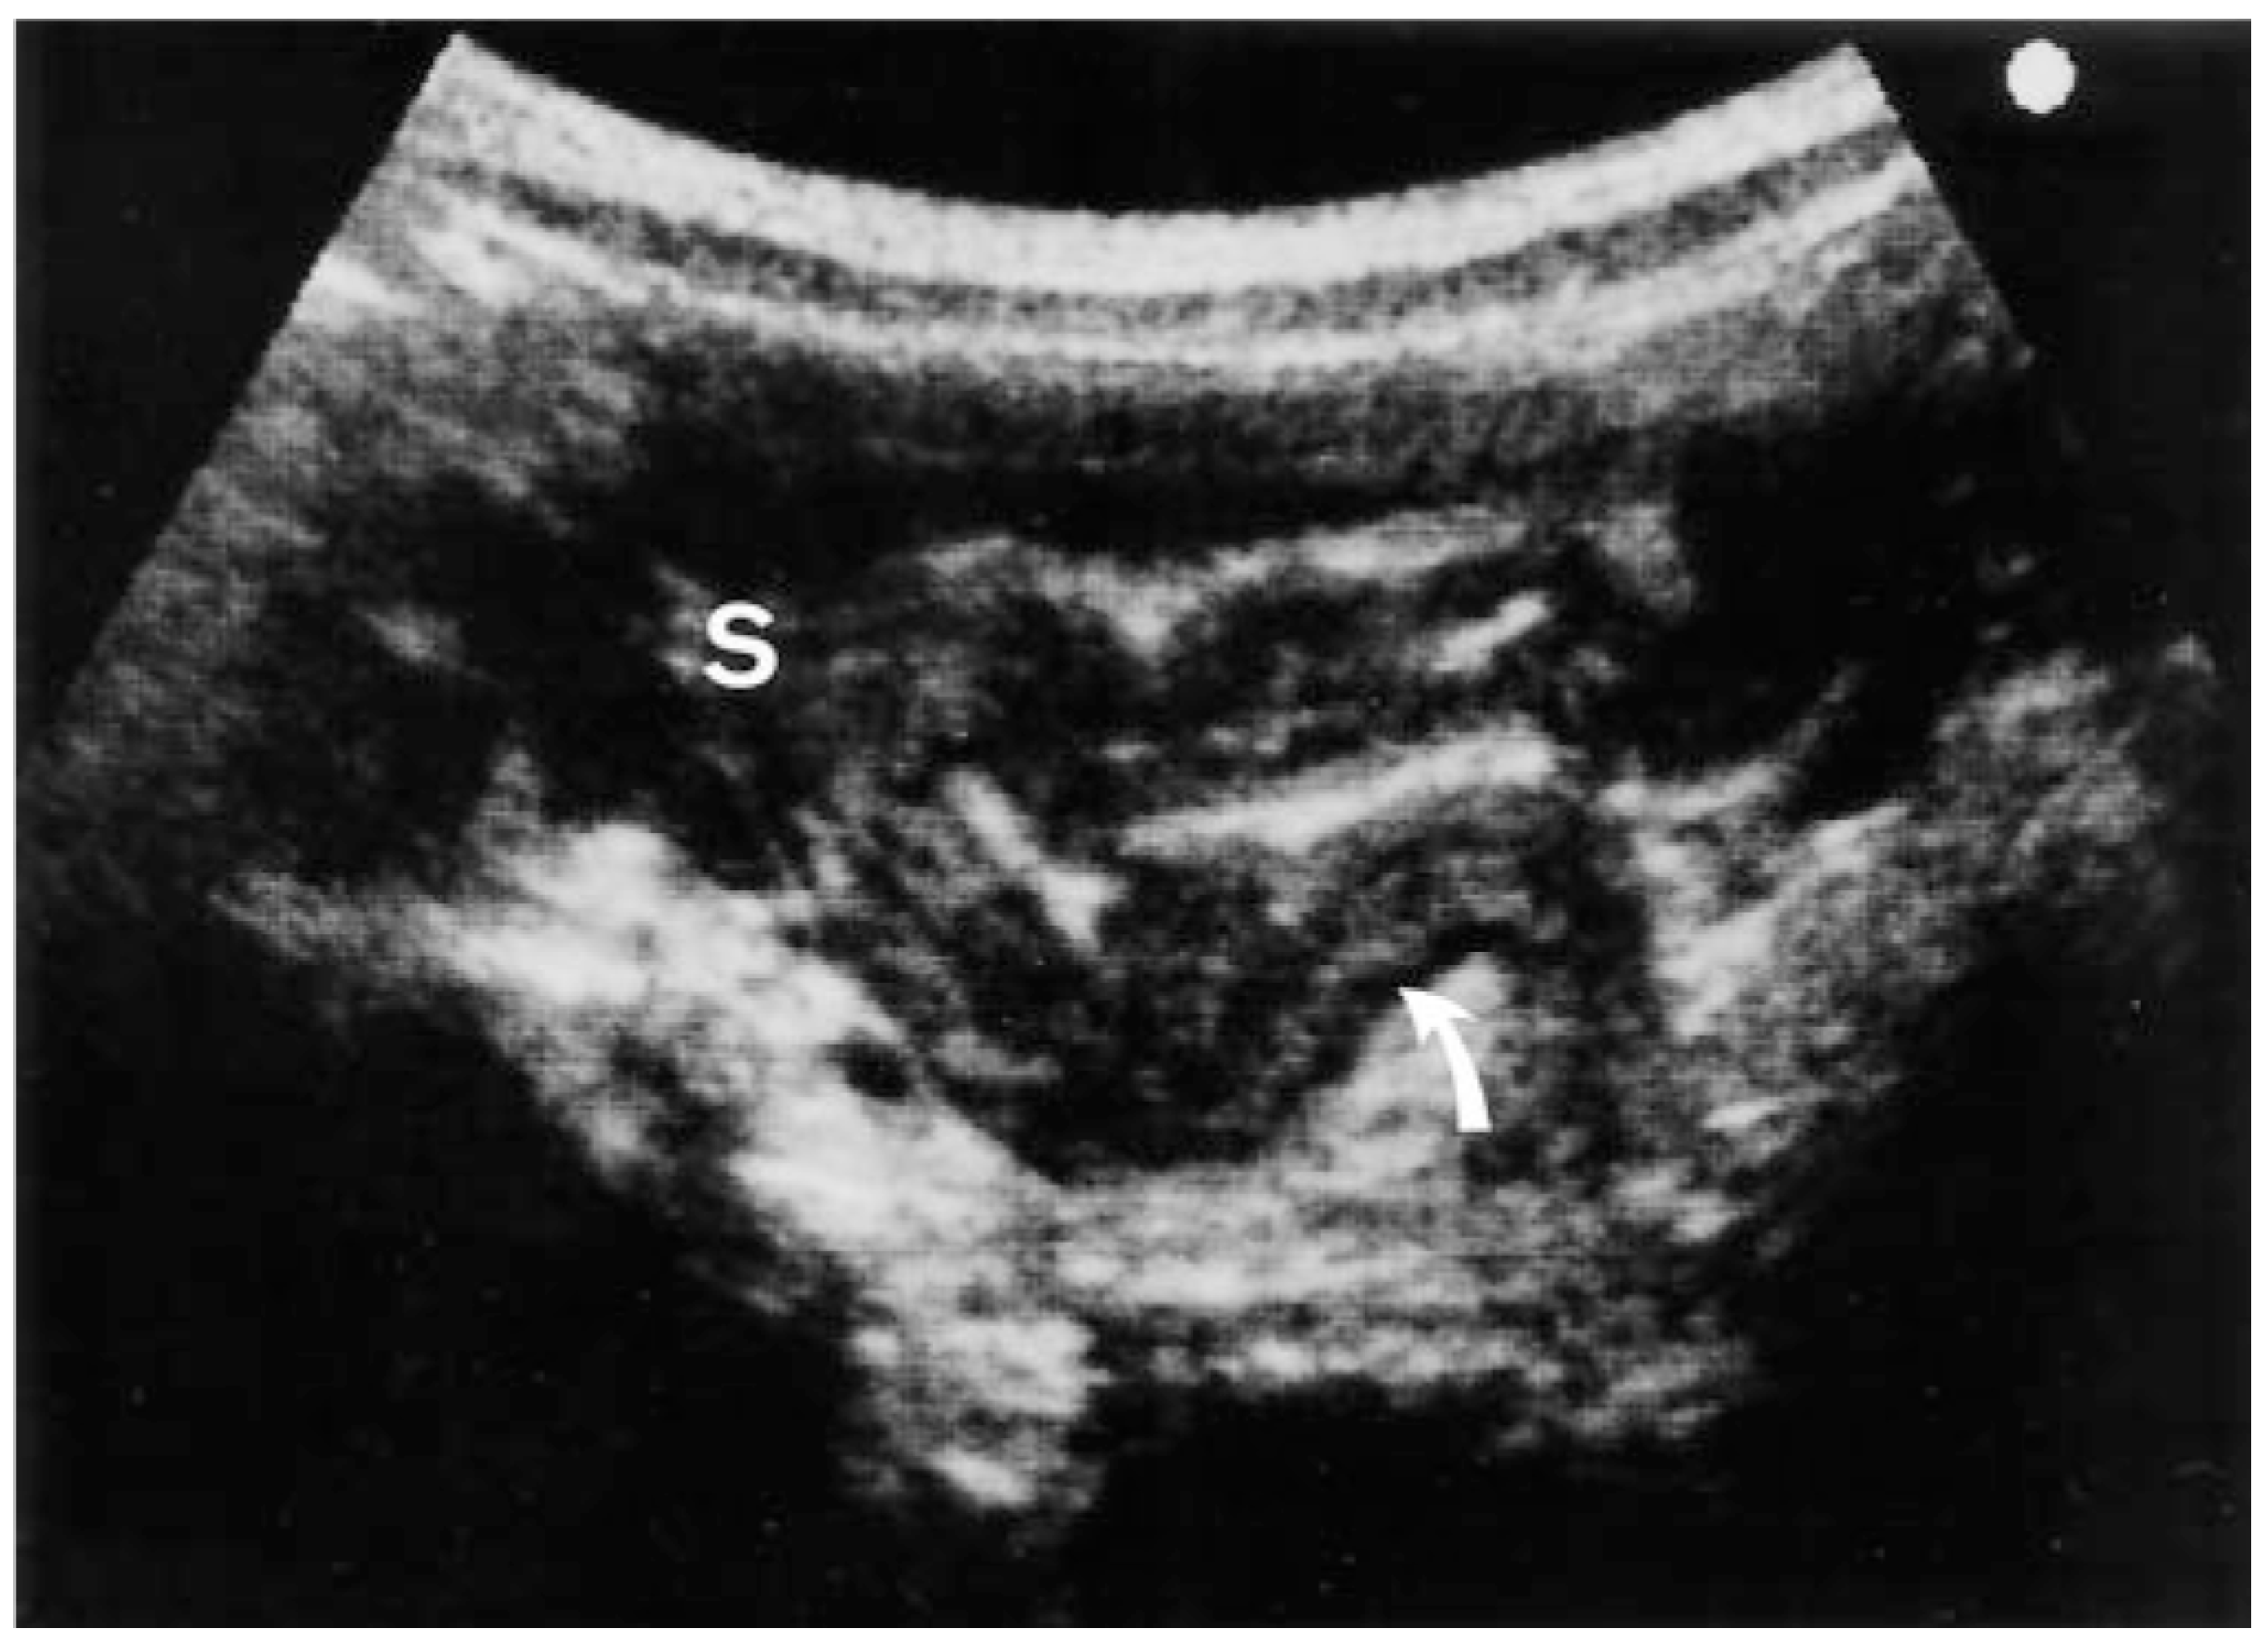

- Ueda, D.; Sato, T.; Yoshida, M. Ultrasonographic assessment of Salmonella enterocolitis in children. Pediatr. Radiol. 1999, 29, 469–471. [Google Scholar] [CrossRef] [PubMed]

- Kucharzik, T.; Kannengiesser, K.; Peterson, F. The use of ultrasound in inflammatory bowel disease. Ann. Gastroenterol. 2017, 30, 10. [Google Scholar] [CrossRef] [PubMed]

- Calabrese, E.; Petruzziello, C.; Onali, S.; Condino, G.; Zorzi, F.; Pallone, F.; Biancone, L. Severity of postoperative recurrence in Crohn’s disease: Correlation between endoscopic and sonographic findings. Inflamm. Bowel Dis. 2009, 15, 1635–1642. [Google Scholar] [CrossRef] [PubMed]

- Rigazio, C.; Ercole, E.; Laudi, C.; Daperno, M.; Lavagna, A.; Crocella, L.; Bertolino, F.; Vigano, L.; Sostegni, R.; Pera, A.; et al. Abdominal bowel ultrasound can predict the risk of surgery in Crohn’s disease: Proposal of an ultrasonographic score. Scand. J. Gastroenterol. 2009, 44, 585–593. [Google Scholar] [CrossRef] [PubMed]

- Conti, C.B.; Giunta, M.; Gridavilla, D.; Conte, D.; Fraquelli, M. Role of Bowel Ultrasound in the Diagnosis and Follow-up of Patients with Crohn’s Disease. Ultrasound Med. Biol. 2017, 43, 725–734. [Google Scholar] [CrossRef]

- Valette, P.J.; Rioux, M.; Pilleul, F.; Saurin, J.C.; Fouque, P.; Henry, L. Ultrasonography of chronic inflammatory bowel diseases. Eur. Radiol. 2001, 11, 1859–1866. [Google Scholar] [CrossRef]

- Roccarina, D.; Garcovich, M.; Ainora, M.E.; Caracciolo, G.; Ponziani, F.; Gasbarrini, A.; Zocco, M.A. Diagnosis of bowel diseases: The role of imaging and ultrasonography. World J. Gastroenterol. 2013, 19, 2144–2153. [Google Scholar] [CrossRef]